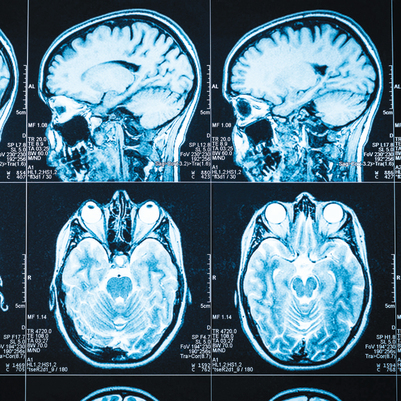

כמוצא אחרון, הנוירוכירורגים הציעו לו "גירוי מוחי". את ההליך הזה אפשר לבצע בצורה ישירה: לפתוח את הראש ולנסות להחדיר מחט או סיב, שיגרו את העצבים באזור האחראי לרעד. החיסרון: מדובר בשיטה פולשנית שעלולה לפגוע באזורים אחרים. את אותו אפקט אפשר להשיג גם בגירוי מוחי באמצעות "הפגזה" אלחוטית של גלי קול (אולטרה־סאונד) מחוץ למוח.

את ההליך מנהל ד"ר ציון זיבלי, נוירוכירורג בכיר בשיבא, ששב לאחרונה מארה"ב. אחרי כמה "הפגזות" במכשיר התהודה המגנטי (MRI), הנעשות בשיתוף פעולה בין אנשי מחשבים לרופאים, שואלים את המטופל לשלומו, והוא מסוגל לענות. כעבור כמה שעות ההליך מסתיים ואז מגישים לפציינט כוס מלאה במים. כולם – ד"ר זיבלי וצוות הרופאים, הסטאז'רים, האחיות, אנשי המחשבים, אשתו של המטופל ואני – מביטים בו במתח.

רמז לקראת העתיד הזה נמצא במחקר שפורסם בחודש שעבר, ובו הצליחו מדענים לגלות "טביעת אצבע" של המוח. במחקר, שנערך על ידי אמילי פיין, דוקטורנטית במחלקה למדעי המוח באוניברסיטת ייל בארה"ב, יחד עם חוקרים אחרים, הצליחו החוקרים לצלם בהדמיה בתהודה מגנטית תפקודית (fMRI) תופעה הנקראת "טביעת אצבע קוגניטיבית".

במחקר, שפורסם בכתב העת "Nature Neuroscience", הגיעו המדענים לדיוק של כמעט 90 אחוז בהבנה מי האדם שלו שייך המוח שנחקר, מתוך כמה עשות נחקרים – וזאת בלי לראות כלל את האדם ובלי לדבר איתו. הם עשו זאת רק באמצעות סריקה של פרופיל הקישורית התוך־מוחית של הנחקרים. במאמרם מציינים החוקרים עוד, כי בהמשך יוכלו לנבא את רמת האינטליגנציה של כל אחד, רק באמצעות סריקה של המוח, וכאמור – בלי לפגוש כלל את האדם שלו הוא שייך (ר' מסגרת).